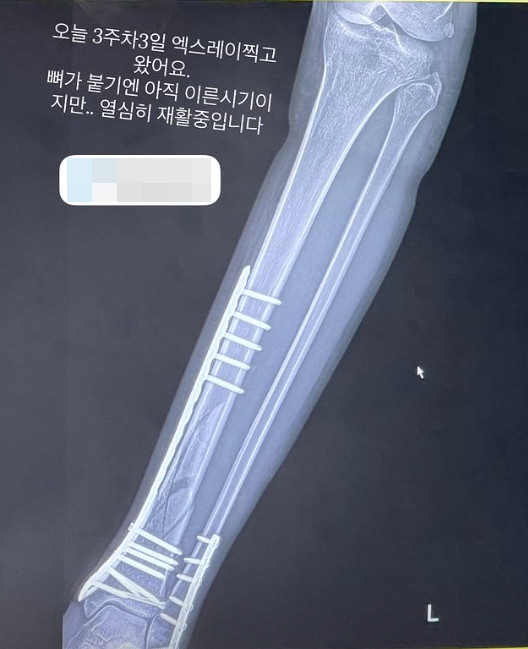

지난 12일 엄지원이 자신의 SNS에 엑스레이 사진을 공유했다. 엄지은 "오늘 3주차3일 엑스레이 찍고 왔어요. 뼈가 붙기엔 아직 이른시기지만... 열심히 재활중입니다"라는 멘트와 함께 재활 사실을 알렸다.